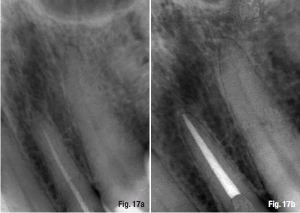

Một phương pháp khác, được ủng hộ bởi một nhóm các học giả nổi tiếng và các nhà lâm sàng giàu kinh nghiệm, tán thành rằng việc sửa soạn và trám bít trong những trường hợp như trên thì luôn chấm dứt tại lỗ chóp giải phẫu hay lỗ chóp trên X-quang, chóp răng trên X-quang. Hình 11a và b minh họa khả năng điều trị thành công càng lớn khi điểm kết thúc của tất cả các thao tác trong ống tủy nằm tại lỗ chóp giải phẫu, không phân biệt loại viêm quanh chóp. Nếu có thể, mục tiêu của điều trị triệt để là để tránh phẫu thuật quanh chóp (Hình 12a–c).

trường hợp viêm quanh chóp

Hình 11a & b: Trong các trường hợp có viêm quanh chóp, điểm cuối cùng nên tại điểm kết thúc của ống tủy, gần với lỗ chóp giải phẫu: hình ảnh trước điều trị (a; với sự giúp đỡ của Tiến sĩ Julian Webber); kiểm tra sau 2 năm (b).